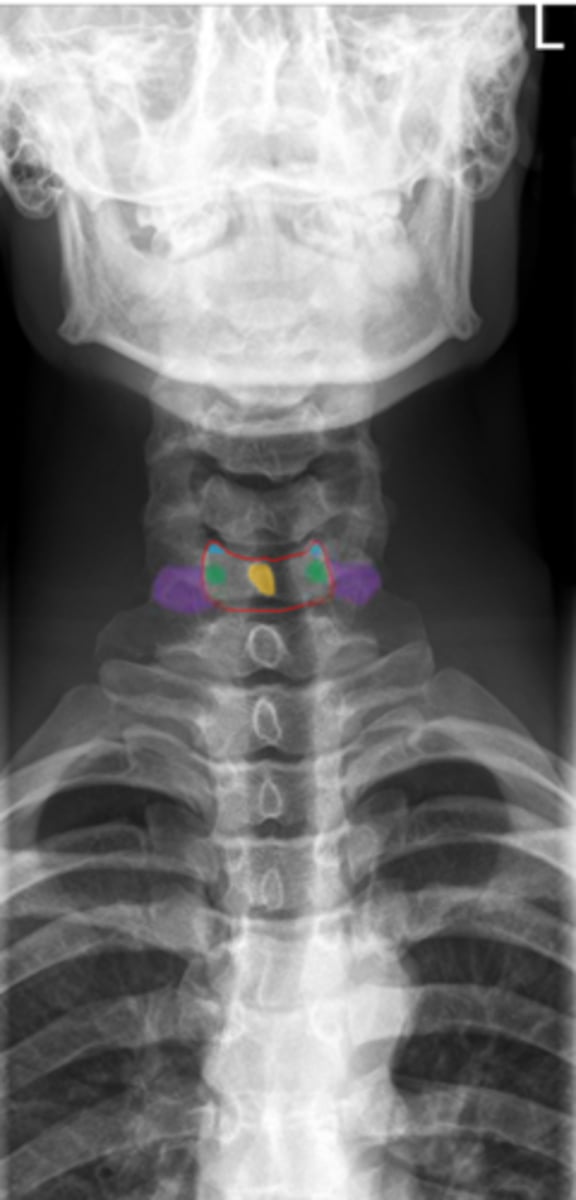

uncinate process

Identify the blue structure

transverse process

Identify the purple structure

pedicles

Identify the green structure

spinous process

Identify the yellow structure

C1 and C2

What vertebrae is being examined?

Odontoid process (dens)

Identify the purple structure

anterior arch/tubercle

Identify the red structure

posterior arch/tubercle

Identify the green structure

lateral masses

Identify the blue structure